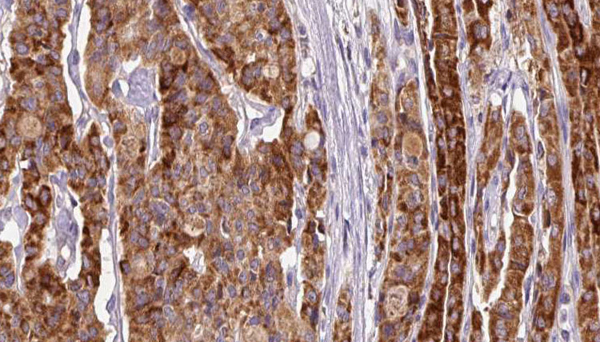

IHC (Immunohistochemistry)

(AAA321353 at 1/100 staining Human thyroid cancer tissue by IHC-P. The sample was formaldehyde fixed and a heat mediated antigen retrieval step in citrate buffer was performed. The sample was then blocked and incubated with the antibody for 1.5 hours at 22 degree C. An HRP conjugated goat anti-rabbit antibody was used as the secondary.)